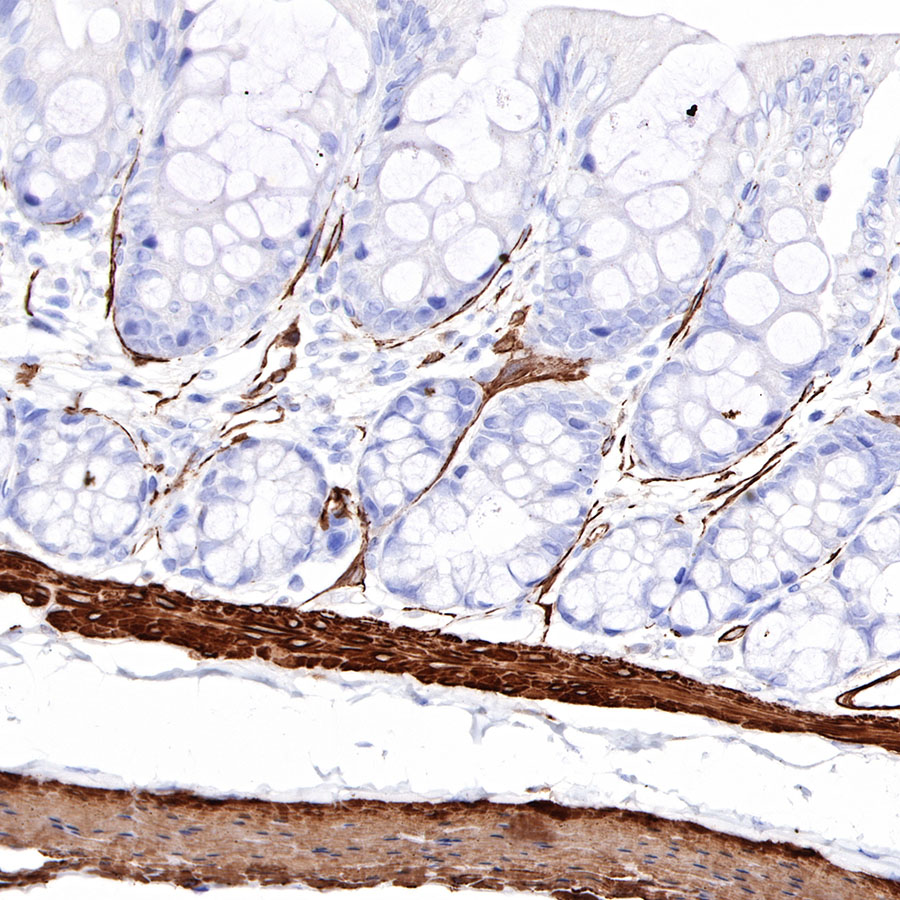

Immunohistochemistry